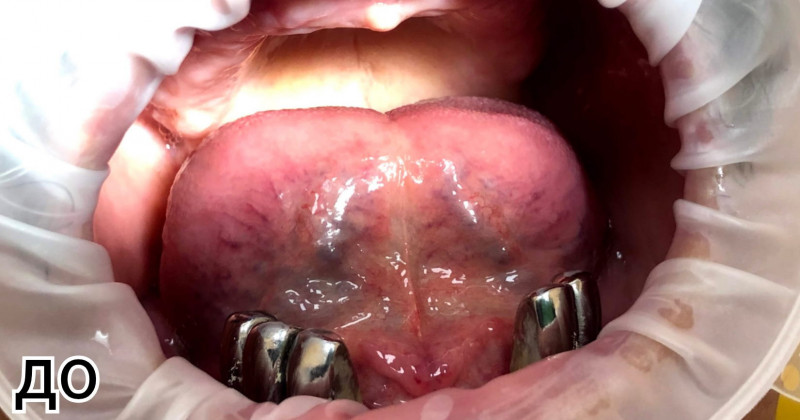

Имплантация Все-на-6 (All-on-6)

Пациентка обратилась в клинику с полным отсутствием зубов на верхней челюсти. Съёмный пластиночный протез, которым она пользовалась, вызывал постоянный кашель. Хирургом были установлены 6 имплантов. Впоследствии на них был зафиксирован протез на диоксиде циркония, облицованный керамикой — метод «Всё на 6-ти».

Доктор: Михальский Константин Станиславович